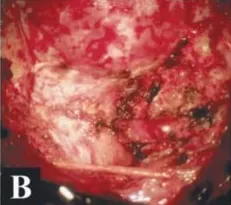

術(shù)中及腫瘤切除后的硬膜內(nèi)部位

枕骨大孔腦膜瘤CT圖片

枕骨大孔腦膜瘤MR圖片

術(shù)后CT和MR,顯示腫瘤及其被腫瘤侵犯的骨質(zhì)都切除,腫瘤全切,Simpson一級(jí)切除。